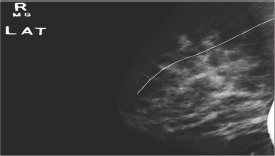

This retrospective study included all patients who underwent HWL at the RBWH, Brisbane, Queensland, Australia, from January 2013 to December 2015. The study was approved by the local ethics committee at the RBWH. We accessed the hospital database to collect the study population. Radiologic and pathologic results were recorded from the electronic medical record. A total of 141 pre-operatives HWL were performed using Hawkins TM III and D Wire (Breast Localization Needles by Argon Medical Devices). All targeted lesions were impalpable. Palpable lesions were excluded. We also excluded cases that were diagnosed in our institution but where the surgical procedures were performed at another centre. Cases that required re-excision but were performed at another centre were also excluded from our study. All HWL were performed on the day of surgery by five radiologists under either tomosynthesis (Figure 1) or ultrasound (Figure 2) guidance, according to the type of lesion localised. Post-localisation 2-view mammogram was performed to document position of the wire (see Supporting Information Figure 1). Post-surgical specimen radiography was performed to verify retrieval of the target and wire, and to radio logically assess surgical margins. Surgical margins were deemed positive if malignancy extended to the edge of specimen, and close if malignancy extended to less than 3 mm.

Figure 1: Tomo synthesis-guided hook-wire localisation of the left breast A) cranio-caudal and B) lateral views show localisation of a post biopsy marker clip at the upper outer quadrant.